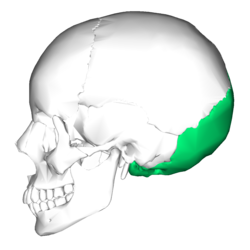

Africanus schrieb:Meine Abbildung zeigt, an welcher Stelle des Schädels der "occipital bone" tatsächlich liegt, während Deine Abbildung den Anschein entstehen lässt, dass dieser höher am Schädel liege. Das nenne ich manipulativ.

Africanus schrieb:Meine Abbildung zeigt, an welcher Stelle des Schädels der "occipital bone" tatsächlich liegt, während Deine Abbildung den Anschein entstehen lässt, dass dieser höher am Schädel liege. Das nenne ich manipulativ.

Deine Quelle:

Wikipedia: Occipital bonevon derselben Quelle.

Vergleiche mit meinem Bild- es gibt keinen Unterschied:

Original anzeigen (0,2 MB)Dein Manipulationsvorwurf ist also einfach nur lächerlich. Vielleicht lebst du in einer Welt in der zwei räumliche Dimensionen existieren und kannst Darstellungen dreidimensionaler Objekte aus verschiedenen Perspektiven nicht verstehen?

Mach dich nicht lächerlich- wenn es um Perspektive geht, passt meine Darstellung besser zu den Hinterkopffotos als deine.

Ich dachte es würde dich freuen- schließlich ist im Autopsiebericht von der Eintrittswunde im occipitalen Knochen die Rede!